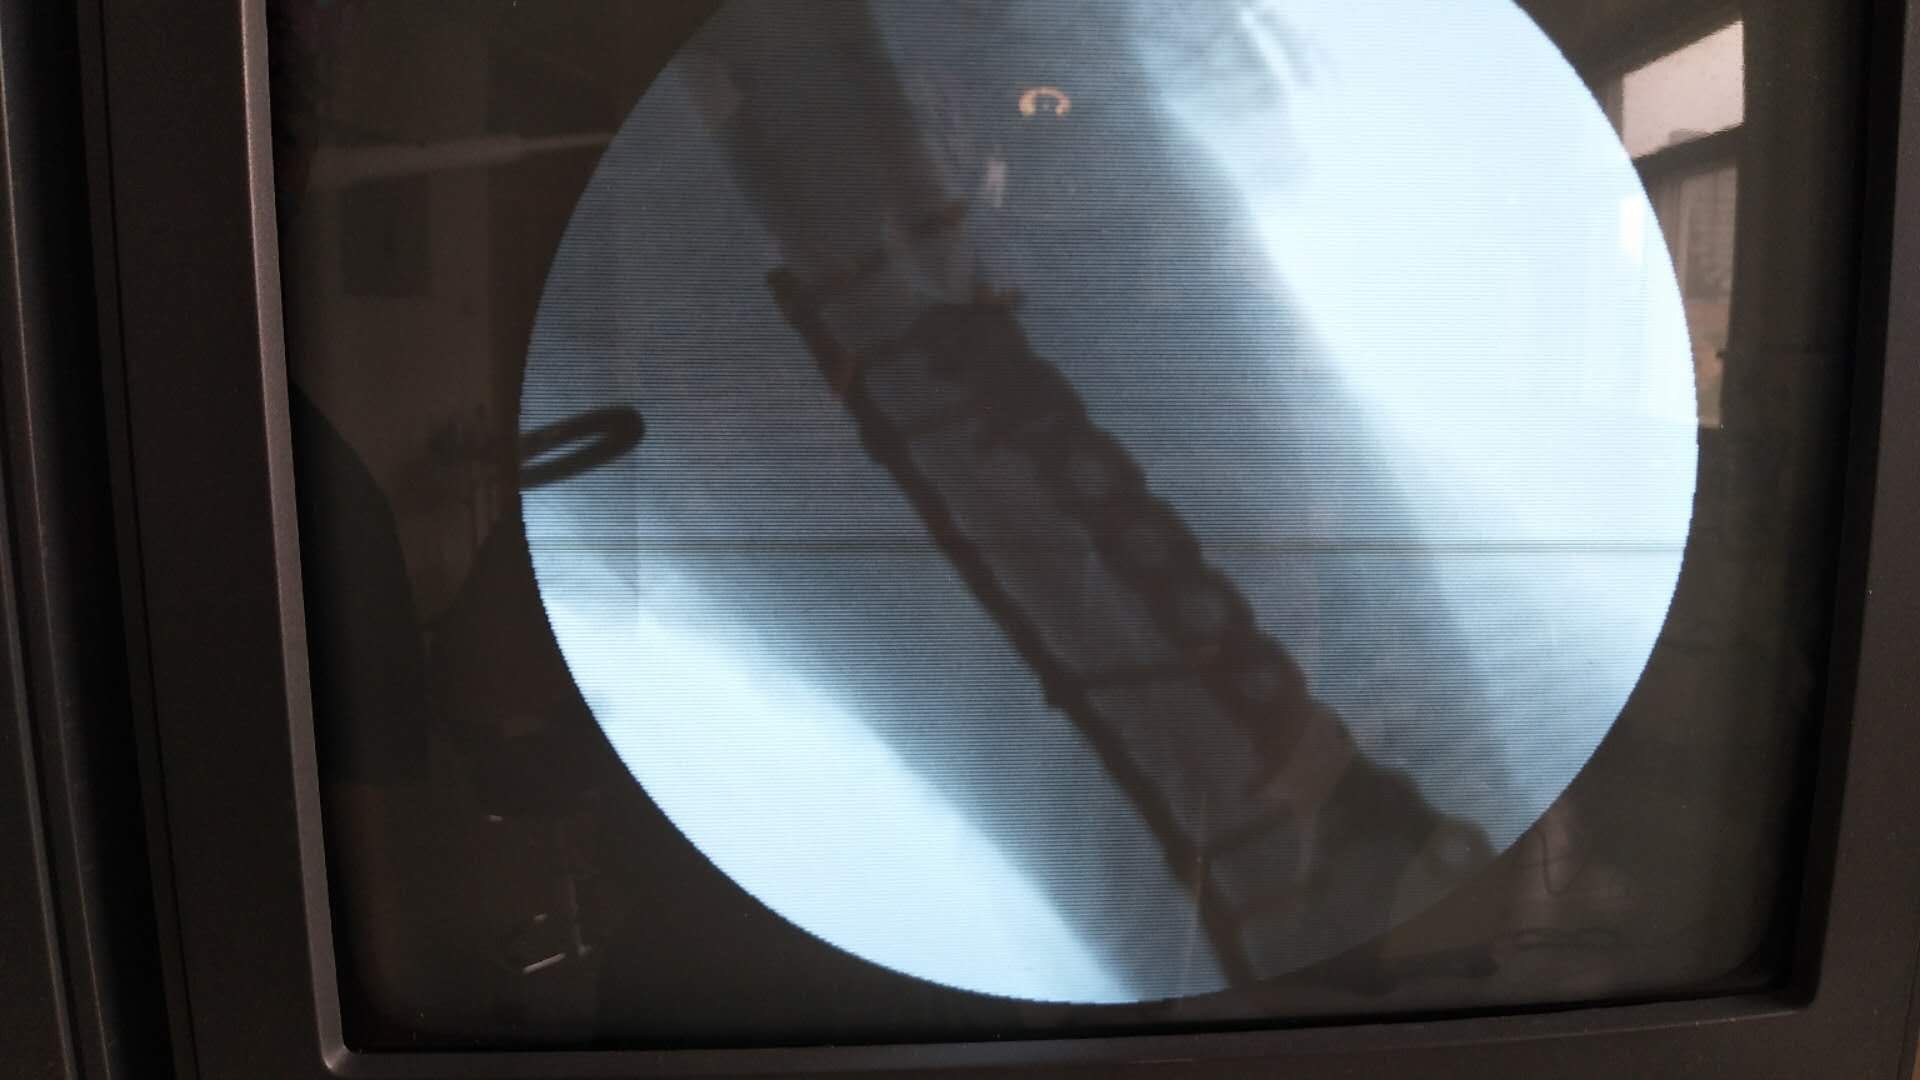

肱骨远端骨折(切复双钛板内固定)

摔伤后右肘部肿胀,畸形,活动受限2小时入院。既往身体健康,无特殊不良嗜好。从事健身教练工作数年。

生命体征平稳,心肺复未见异常。右上臂肿胀明显,畸形,局部皮色发红,皮温高,压痛及纵叩痛阳性,可及骨檫音及骨檫感,异常活动,末梢血运感觉正常。

诊断肱骨远端骨折在臂丛麻醉下行切复内固定术,术后抗炎,消肿等处理。